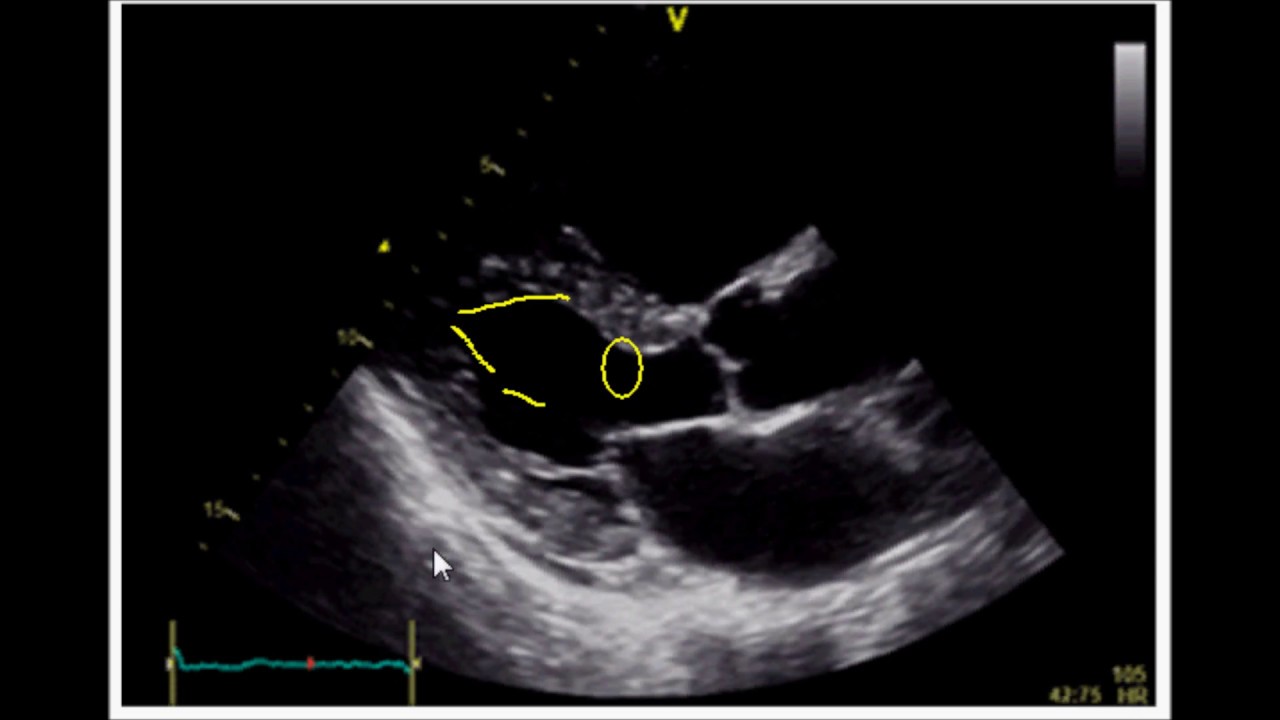

Метод Симпсона: эхокардиография

Привет, ребята! В этом видео я покажу вам, как применить метод биплана Симпсона для оценки фракции выброса.